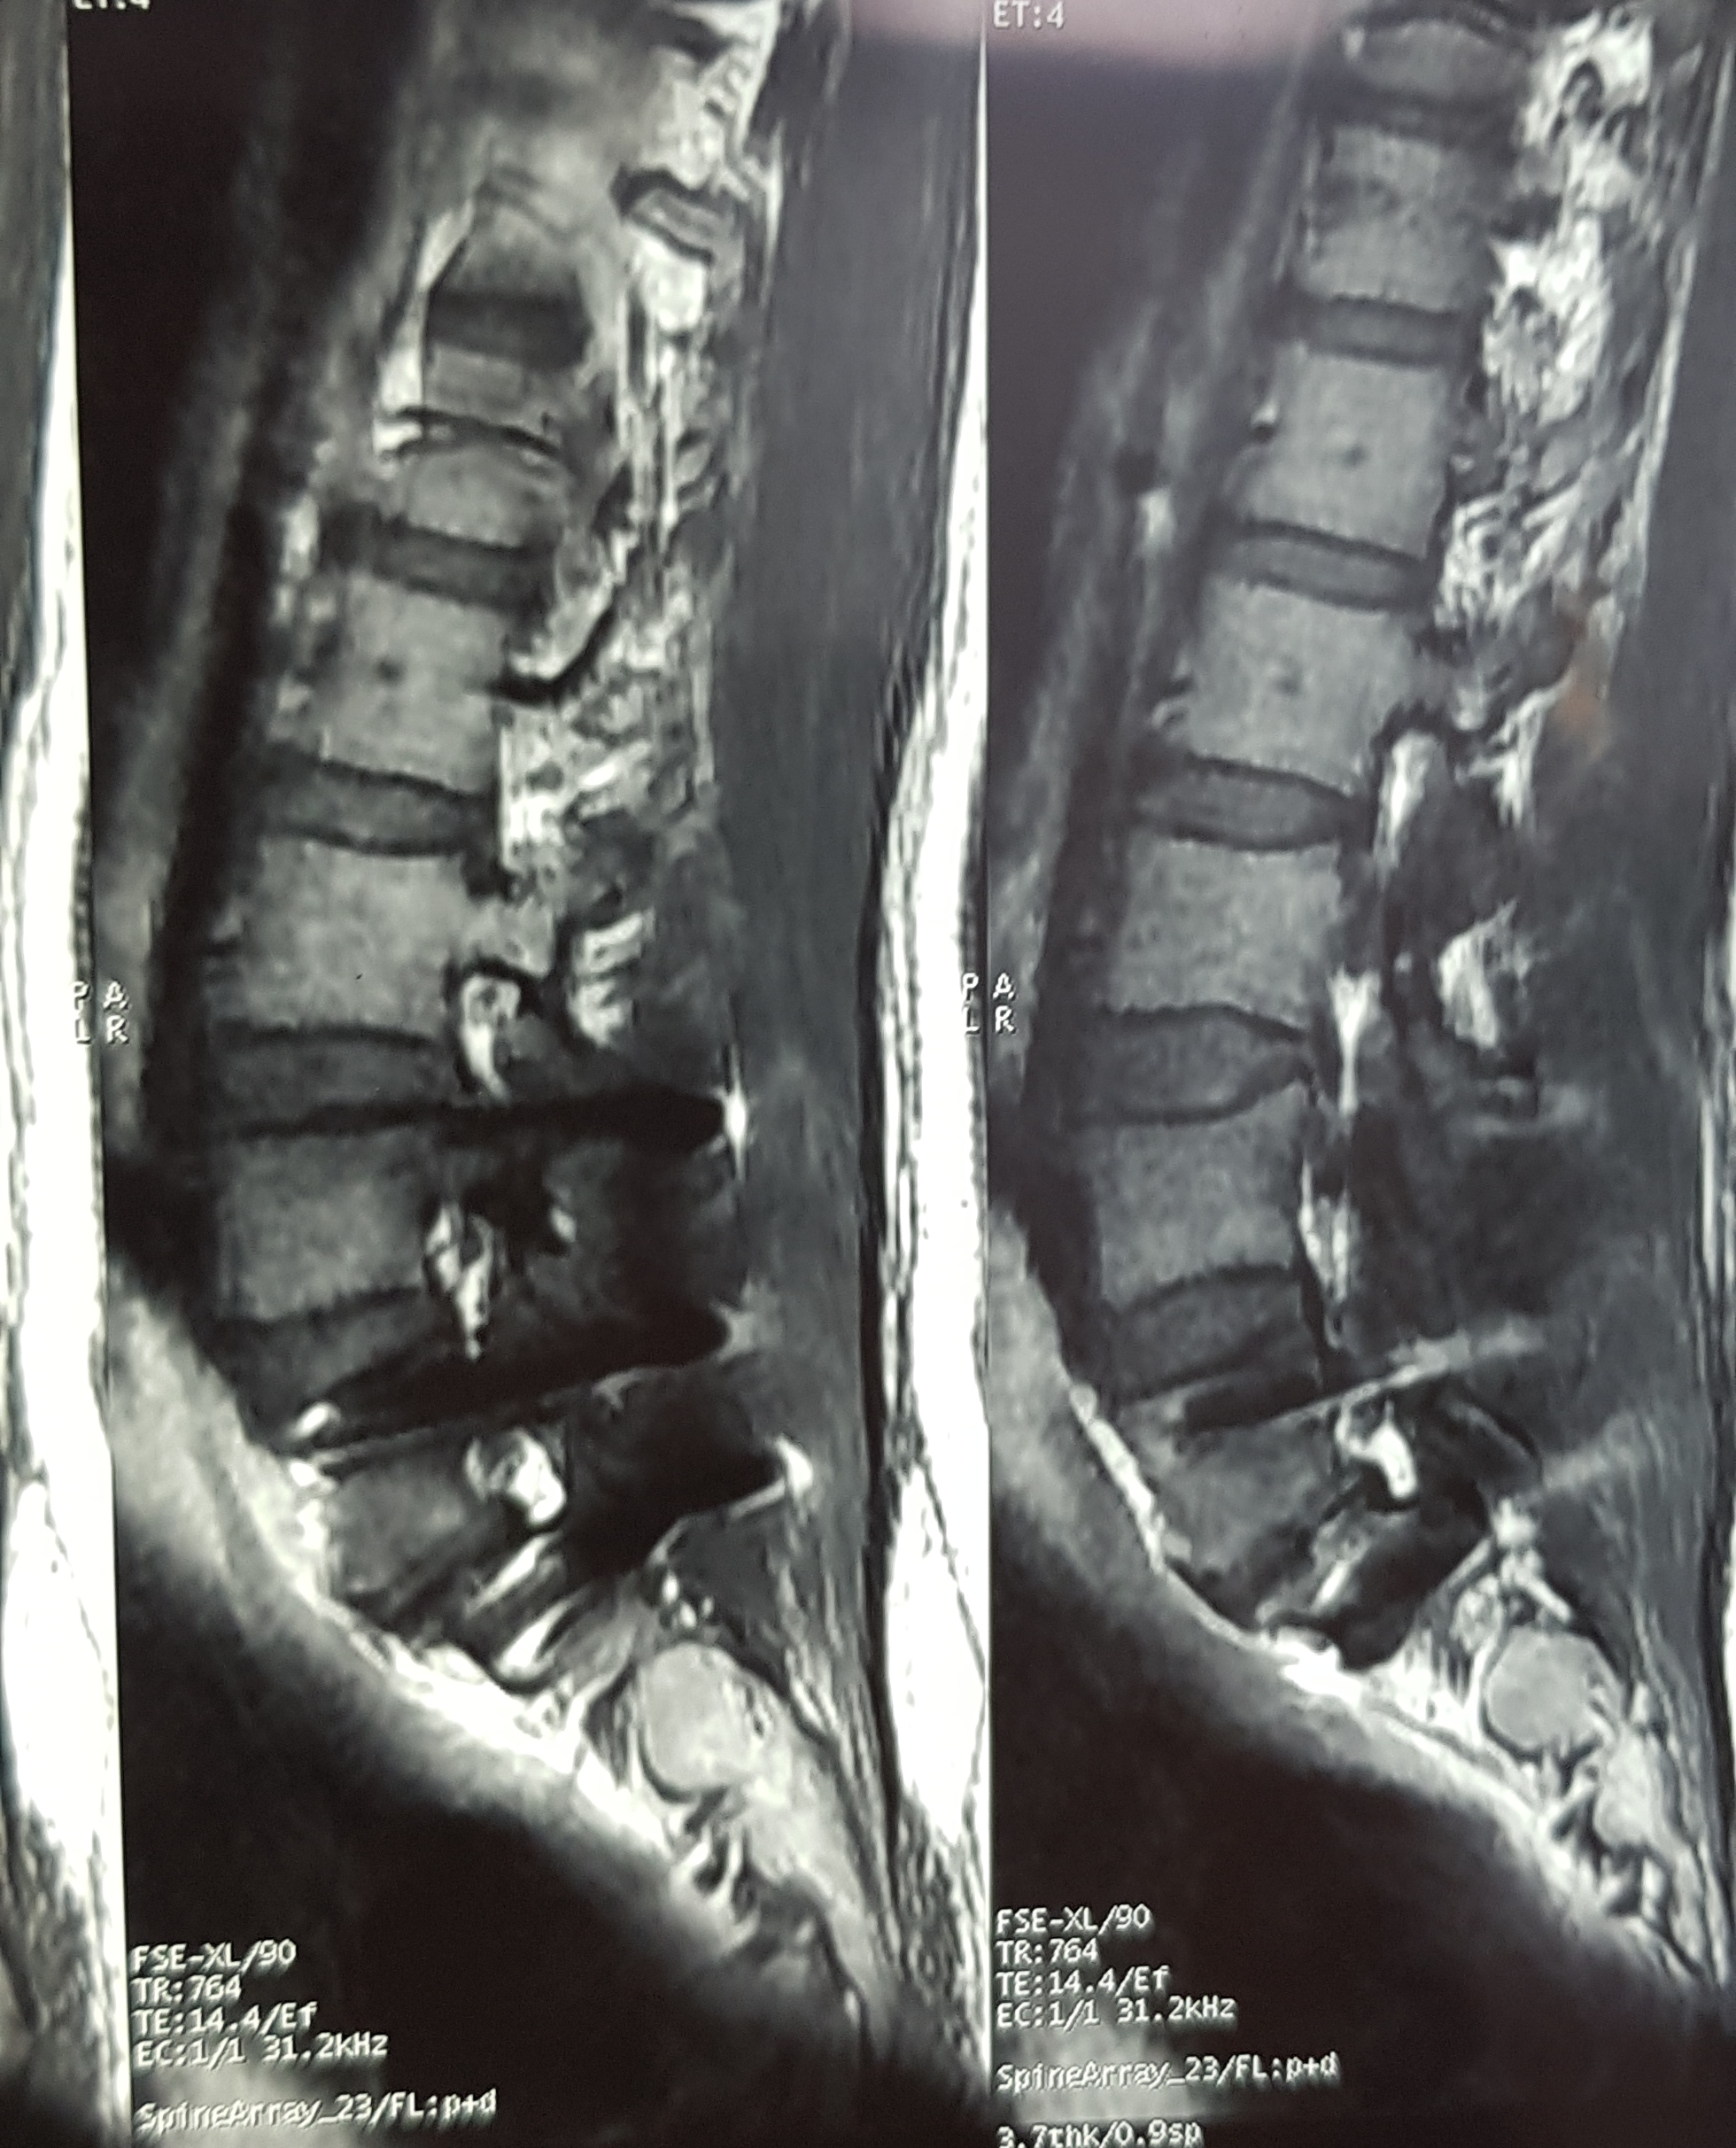

بعد از یکماه برای ویزیت دوباره به کلینیک آمد .حالش بهتر شده بود .بدون درد راه می رفتت و گز گز پاهاش تا ۵۰ درصد کمتر شده بود .مهمتر اینکه میخندید و روحیه اش کاملا عوض شده بود . موقع رفتن از مطب ام ار ای قبل عمل جراحیش رو دوباره از پاکت در آورد(عکس سمت راست) و با خنده ای تلخ به من گفت : آقای دکتر ای کاش عمل نمی کردم ..درسته ؟؟؟؟؟